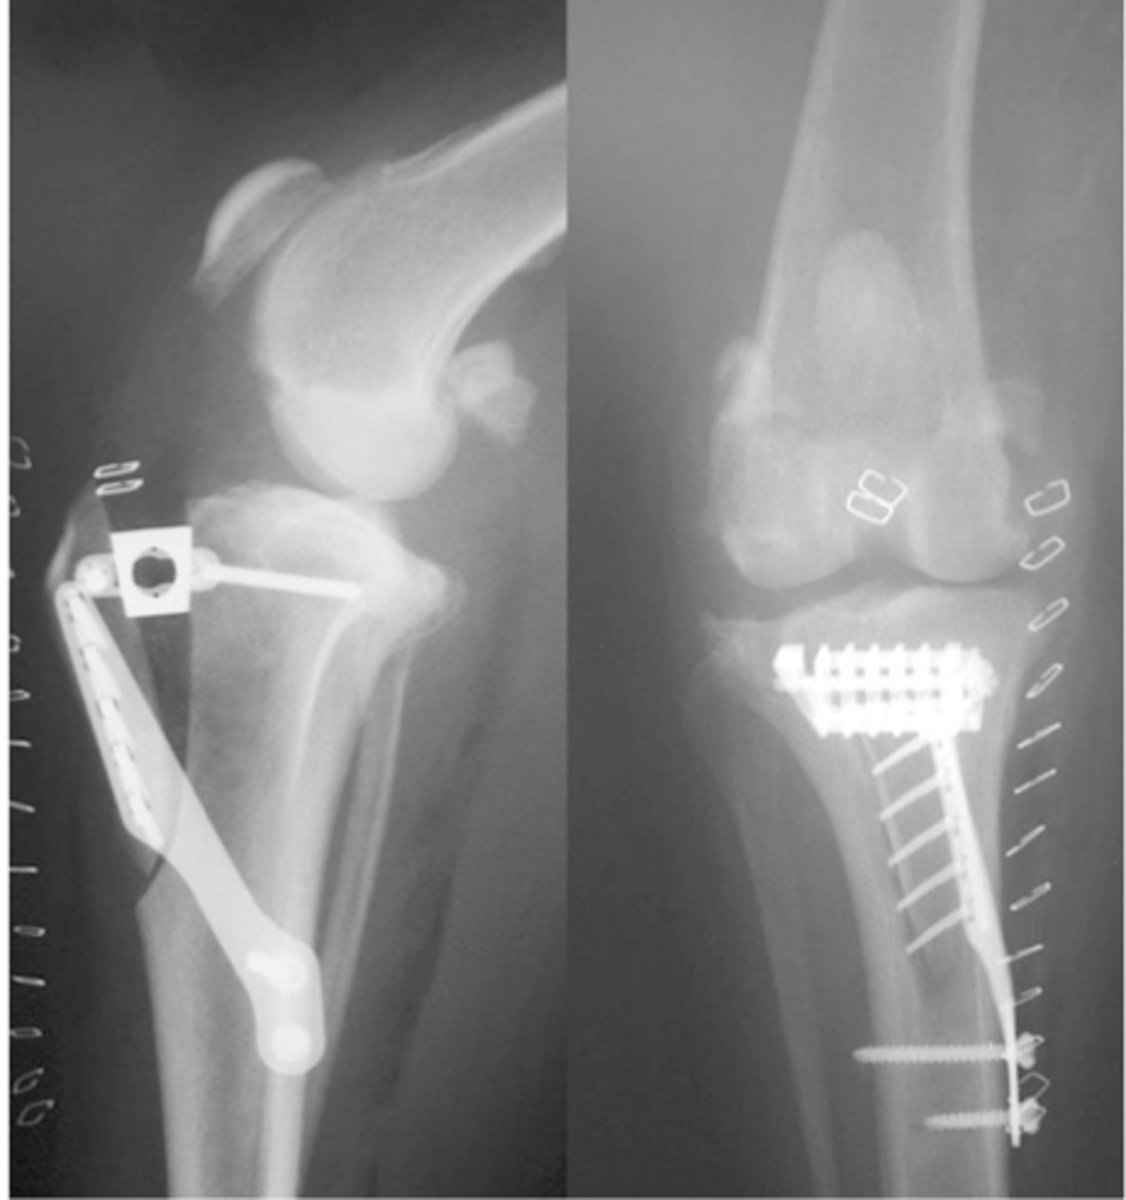

post-op RADS of TTA

what is shown here